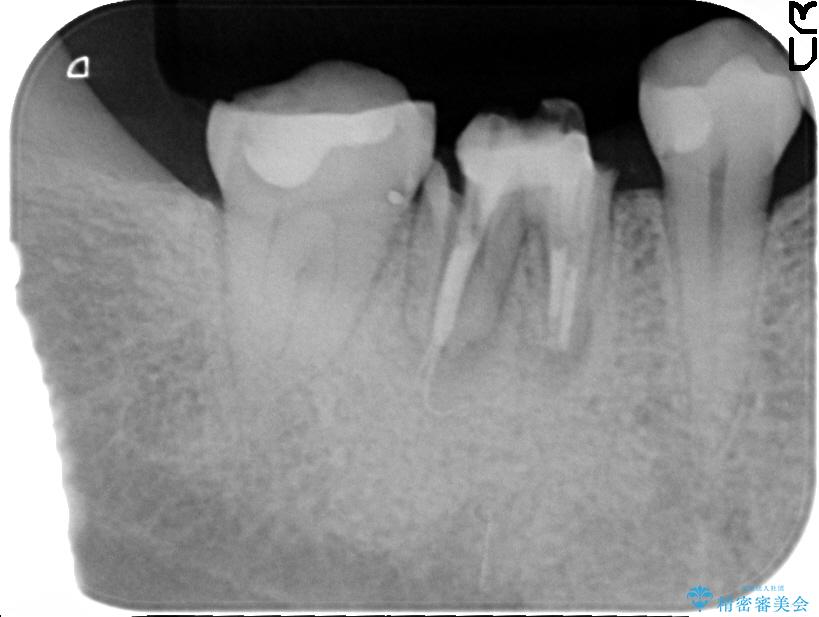

精密な検査を行ったところ、根が完全に折れている為、抜歯が必要となりました。抜歯後は骨と歯茎が痩せてしまう事がないように、人工の骨をつめ、インプラント治療を行う計画としました。